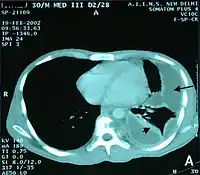

تصوير صدري مقطعي محوسب يُظهر تدمي صدري على الجانب الأيسر (السهم الأسود)، من مضاعفات التهاب المفصل الروماتويدي